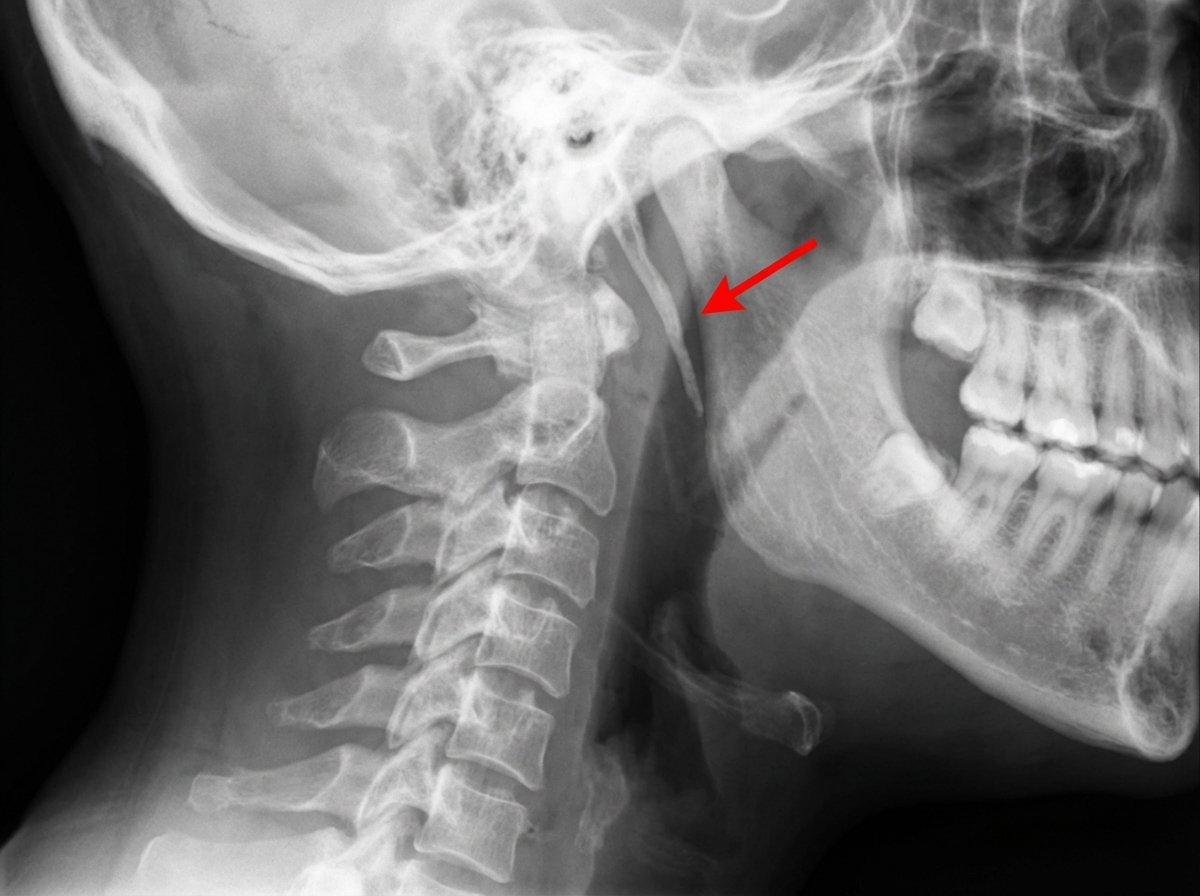

The X-ray shown below is diagnostic of what? The finding in the X-ray is marked with a red arrow.

Explanation: ***Eagle syndrome*** - X-ray shows **elongated styloid process** (>25mm) which is pathognomonic for Eagle syndrome, causing **throat pain** and **dysphagia**. - The **calcified stylohyoid ligament** or elongated styloid process is clearly visible on plain radiographs, making this a definitive radiological diagnosis. *Trigeminal neuralgia* - This is a **clinical diagnosis** based on characteristic **sharp, electric shock-like pain** in trigeminal nerve distribution. - **No specific radiological findings** are seen on plain X-rays; diagnosis relies on clinical presentation and sometimes MRI. *Cervical cord compression* - Requires **MRI or CT myelography** to visualize cord compression and cannot be diagnosed on plain X-rays. - Plain radiographs may show **degenerative changes** but cannot demonstrate actual cord compression or neurological involvement. *Non specific myalgia* - This is a **clinical syndrome** with muscle pain and tenderness without any radiological abnormalities. - **Normal X-ray findings** are expected, and diagnosis is based purely on clinical examination and history.